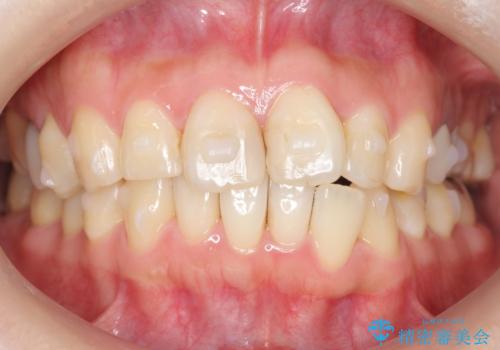

前歯の歯並びが気になる マウスピース矯正 30代女性

- 前歯の歯並びが気になることを主訴に来院された患者様です。

接客業のためインビザライン(マウスピース矯正)をご希望されました。

顎が小さく歯を並べるためのスペースが足りないため、

上下の前歯の歯と歯の間をすく処置(ディスキング)を行いました。

矯正装置:インビザラインフル (初回13stage+リファインメント11stage:計1年)

矯正後、右上5左上45セラミッククラウン・右下65左下5セラミックインレーによる補綴治療を行いました。